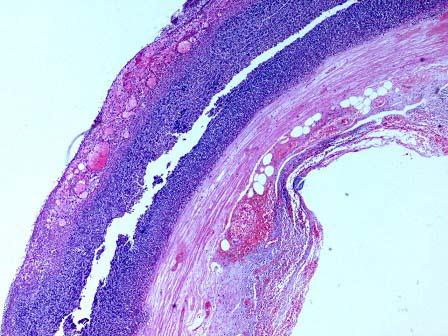

问题 患者男性,42岁,持续性剧烈腹痛3小时伴恶心、呕吐,拟诊“急性阑尾炎”手术。术中见阑尾呈紫黑色,根部破裂。镜检如图,应诊断为 ( )

选项 A.急性蜂窝织性阑尾炎伴穿孔 B.坏疽性阑尾炎伴穿孔 C.慢性阑尾炎伴穿孔 D.阑尾脓肿 E.阑尾腺瘤

答案 B